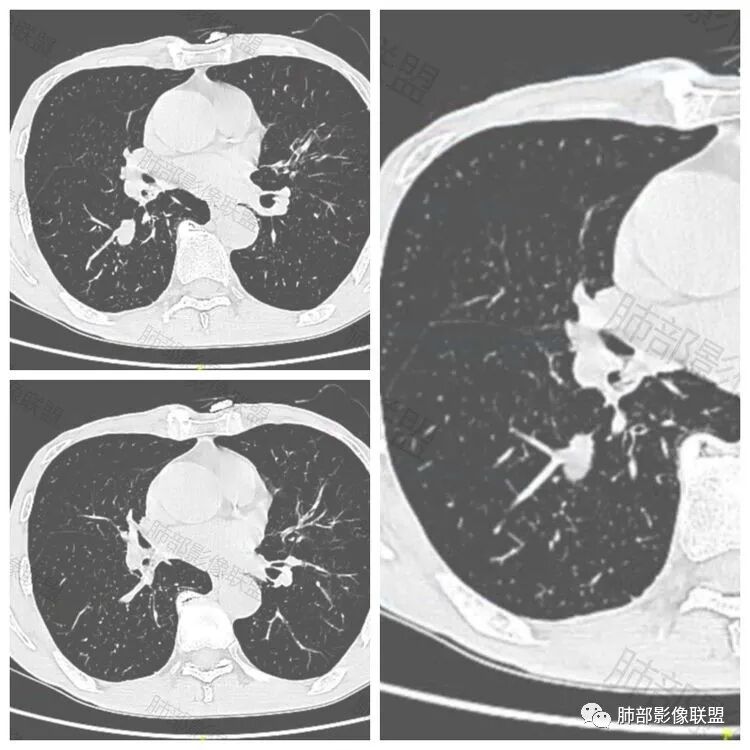

许慧良:

老年男性患者,胸部隐痛1月入院,有长期吸烟史,胸部CT:右肺下叶背段梭型结节灶,边界清晰,无明显分叶、毛刺及周边磨玻璃影,内部密度不均匀,支气管截断,增强扫描不均匀轻度强化,内部似乎见支气管黏液栓,纵隔淋巴结不大,考虑恶性病变:小细胞癌(缺少典型的纵隔肺门淋巴结增大融合),鳞癌(病史复合,但没有阻塞性肺炎,内部没有坏死,),类癌(多见于女性患者,与吸烟关系不大),首先考虑典型类癌,

飞鹰行动:

老年男性,右肺下叶梭形或椭圆形结节,形态较规则,边缘光整,支气管截断,增强不均匀轻度强化,右肺门及纵隔淋巴结增大,考虑恶性病变,鳞癌或小细胞癌,神经内分泌癌(小细胞形)。

红星:

老年男性患者,右肺下叶背段梭形结节影,边界比较光整,密度均匀,没有明显的分叶毛刺,没有阻塞性肺炎的表现,这些感觉具备有良性的特点。而近端支气管截断,增强明显的强化,纵隔多发的淋巴结,显得是恶性的特点。总体印象,老年患者+支气管截断征象+明显强化的结节+纵隔多发淋巴结,还是考虑恶性结节,小细胞癌或是鳞癌。

必有路:

男性,老年人,长期吸烟史,老慢支背景,右下肺背段占位,支气管亚段门口堵,病灶长轴与支气管平行,推测腔内生长可能,病灶内血管穿行,周围干净,轻度强化,右肺门淋巴结肿大,考虑恶性,神经内分泌癌(大小类)>淋巴上皮瘤样癌>腺癌>鳞癌

宇宙:

右肺下叶梭形实性结节,密度均匀,边缘光整,局部膨隆,近端支气管截断,轻度强化,血管走行自然,右肺门及纵隔淋巴结增大,考虑小细胞癌>鳞癌

王秀仙:

右肺下叶背段结节,沿着支气管走行呈长椭圆形,边缘圆滑清晰,近端支气管阻塞,远端支气管有沿壁增厚,右肺门淋巴结肿大,中度强化,老年男性,吸烟病史,肺气肿背景,考虑小细胞肺癌,鉴别鳞癌

丽:

老年男性,吸烟史,右肺下叶梭形肿块,边缘平直有分叶,支气管近端阻塞,右肺门肿大淋巴结,增强后轻度强化,欠均匀,首先考虑恶性,小细胞肺癌?

阳光:

老年男性+吸烟+右下肺肿块影+支气管截断+淋巴结肿大,考虑恶性,倾向小

小芳:

老年男性,吸烟史,右肺下叶背段梭型软组织肿块,边缘膨隆,不均匀强化,近端支气管截断,同侧肺门及纵隔淋巴结肿大,支持恶性,小细胞可能大,鳞癌缺少阻塞性改变

良孑:

晨读,右下叶梭形占位,边界光滑,支气管截断,可见尾征,不均匀轻度强化,肺门淋巴结肿大,有吸烟史,高龄高危患者,首先考虑恶性,考虑小细胞癌,鉴别一下鳞癌

傅昌瑜:

老年男性,前胸隐痛1月。2年前有白内障手术史。右下肺结节,沿中轴呈梭形,膨隆,边清、无分叶,无毛刺,近端支气管截断完全堵塞,病灶以远未见阻塞性炎症及肺不张。内部密度基本均匀,增强轻微强化,似见局部低密度影。纵隔及右肺门见肿大淋巴结。整体考虑恶性可能性大,小细胞癌?鳞癌?注意鉴别良性结节—错构瘤。

弹指之间:

老年男性,长期吸烟史,右肺下叶背段梭形低密度灶,边界清晰,无明显分叶、毛刺,边缘稍彭隆,支气管截断,右肺门淋巴结增大,增强扫描不均匀轻度强化(延迟略明显),首先考虑恶性,小?不典型结核球待排。

看图说话:

右肺下叶背段结节,气管堵塞,密度均匀,边界清晰,无明显分叶、毛刺,边缘膨隆,右肺门淋巴结增大,增强轻度强化,考虑小细胞癌,鉴别鳞癌。

自信人生:

右肺下叶梭形软组织结节,密度均匀,明显尾巴,边缘光整,近端支气管截断,轻度强化,血管走行自然,又腊肠尾巴征象

考虑恶性  小细胞癌?

流心明智:

男,83,前胸部隐痛不适1月。有长年大量吸烟史。胸部CT:肺气肿,右肺下叶纺锤型实性结节灶,边界清晰,支气管截断,内部密度不均匀,增强扫描不均匀强化,右肺门淋巴结大。考虑恶性病变:小?鳞?鉴别炎性肉芽肿、错构瘤等。

棉花糖:

晨读:老年男性+吸烟+右肺下叶与气管长轴一致的梭形肿块影+支气管截断,轻度强化,右肺门肿大淋巴结,考虑恶性,小细胞肺癌可能,鉴别鳞癌

南边:

有强化吗?

强化就支持恶性

呈典型管状改变,近端支气管堵塞、稍扩张,病灶有强化倾向于恶性,没有强化倾向于炎性病变(结核之类);近端呈结节状(鳞癌多一些),这个病例呈管状(小细胞Ca多一些);平扫与强化有差异,有轻度强化,是粘液栓还是血管?